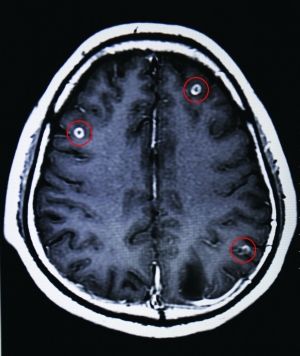

紅圈處為該青年腦中部分寄生蟲

2月18日,省二醫(yī)接診了一位來自廣西的青年,該病人稱自己經(jīng)常頭暈無力,看不清東西。經(jīng)掃描發(fā)現(xiàn),該青年大腦中竟盤踞著19條寄生蟲。

據(jù)省二醫(yī)門診部王主任介紹,此病叫做“腦囊蟲病”,多見于青壯年——吃了豬肉中的豬肉絳蟲蟲卵,經(jīng)消化道進(jìn)入腸壁再進(jìn)入腸系膜靜脈,最后經(jīng)血液循環(huán)將蟲卵送到腦膜、腦實質(zhì)以及腦室內(nèi)。而患病青年也承認(rèn)自己喜歡生吃豬血。

王主任告訴記者,此病雖不是什么疑難雜癥,且也不難醫(yī)治,發(fā)病初期僅靠藥物就可得到控制。但患病如不及時治療,腦組織及大腦中樞則易受損,進(jìn)而引起頭疼、無力、肢體運動障礙癥狀,嚴(yán)重的會引發(fā)癲癇,視物不清,失明甚至死亡。